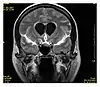

Neuroimaging

MRI is the investigative tool of choice for neurological cancers over CT, as it offers better visualization of the posterior cranial fossa, containing the brainstem and the cerebellum. The contrast provided between grey and white matter makes MRI the best choice for many conditions of the central nervous system, including demyelinating diseases, dementia, cerebrovascular disease, infectious diseases, Alzheimer's disease and epilepsy.[26][27][28] Since many images are taken milliseconds apart, it shows how the brain responds to different stimuli, enabling researchers to study both the functional and structural brain abnormalities in psychological disorders.[29] MRI also is used in guided stereotactic surgery and radiosurgery for treatment of intracranial tumors, arteriovenous malformations, and other surgically treatable conditions using a device known as the N-localizer.[30][31][32] New tools that implement artificial intelligence in healthcare have demonstrated higher image quality and morphometric analysis in neuroimaging with the application of a denoising system.[33]